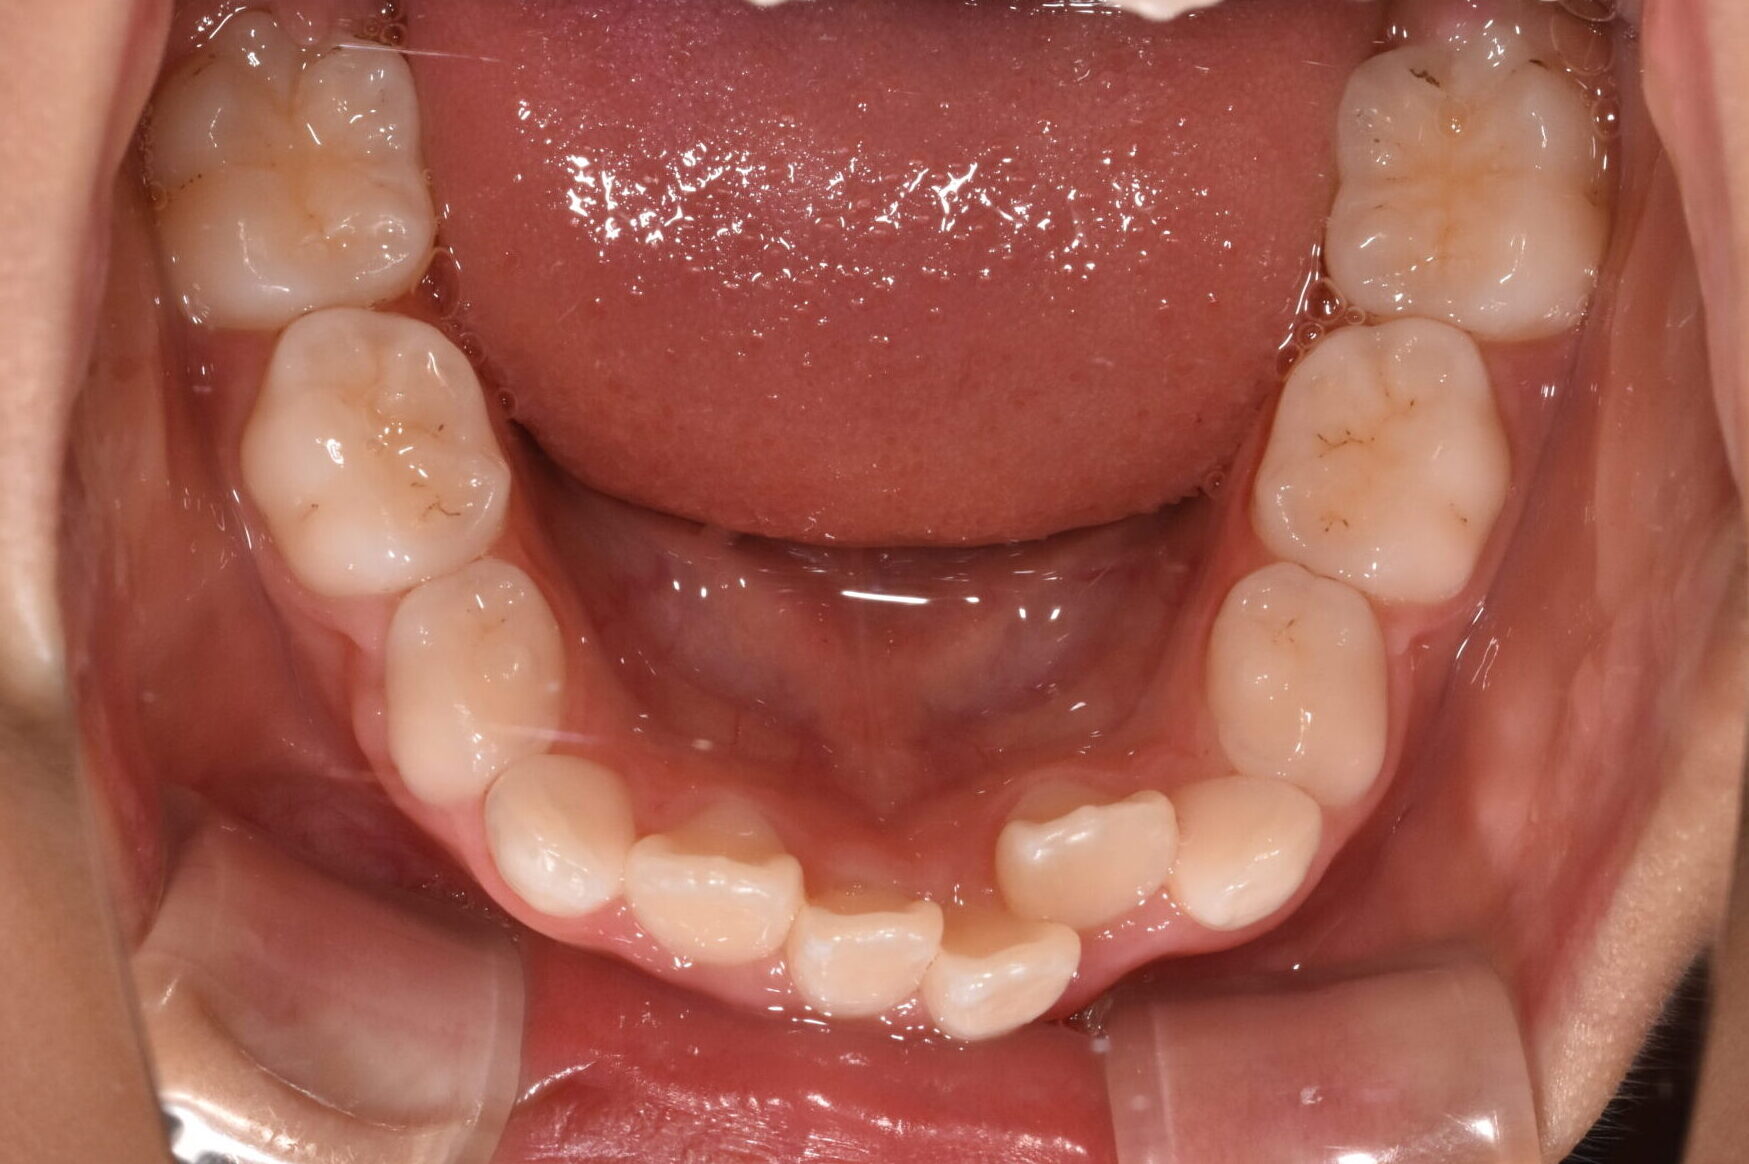

反対咬合・叢生 7歳 女の子

7歳 女性

治療前

年齢:7歳 女の子

お悩み:

前歯が逆に噛んでいる(受け口)

状態:

骨格:受け口傾向

歯並び:前歯のかみ合わせが逆

治療方法:

マウスピース型矯正

治療期間:

3年

治療のポイント:

・成長を利用して改善

・機能(舌・呼吸)も同時にアプローチ